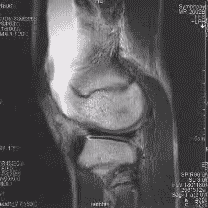

Kreuzbandrisse kommen recht häufig vor. Sie entstehen durch die so genannte Flexions-Valgus-Außenrotations-Stellung. Das heißt, dass das Knie unfreiwillig gebeugt, in die X-Bein-Stellung und nach außen gedreht wird, wobei der Unterschenkel festgestellt ist. Typischerweise entstehen solche Verletzungen beim Skifahren, Handball oder Fußballspielen. Durch das Zerreißen der Bandstrukturen kommt es gleichzeitig zu Gefäßrissen, die eine Blutung in das Kniegelenk (Hämarthros) verursachen. Kreuzbandrisse werden im Schnelltest mittels des vorderen oder hinteren Schubladentests erkannt, d. h. bei gebeugtem Kniegelenk lässt sich das Schienbein gegen den Oberschenkelknochen verschieben und zwar nach vorne (Riss des vorderen Kreuzbands, „vorderes Schubladenphänomen“) oder nach hinten (Riss des hinteren Kreuzbands, „hinteres Schubladenphänomen“). Danach werden die Kreuzbandrisse meist mittels Kernspintomographie diagnostiziert. Behandelt wird ein Kreuzbandriss meistens, indem ein Stück eines anderen Bandes oder einer Muskelsehne entnommen wird, um daraus eine Kreuzbandplastik herzustellen.

Als bildgebende Verfahren werden Röntgenaufnahmen, Sonographie, Arthrographie (kaum mehr angewendet), Magnetresonanztomographie (MRT) und Computertomographie (CT) eingesetzt. Eine Arthroskopie kann zur Darstellung innerer Strukturen angewendet werden.